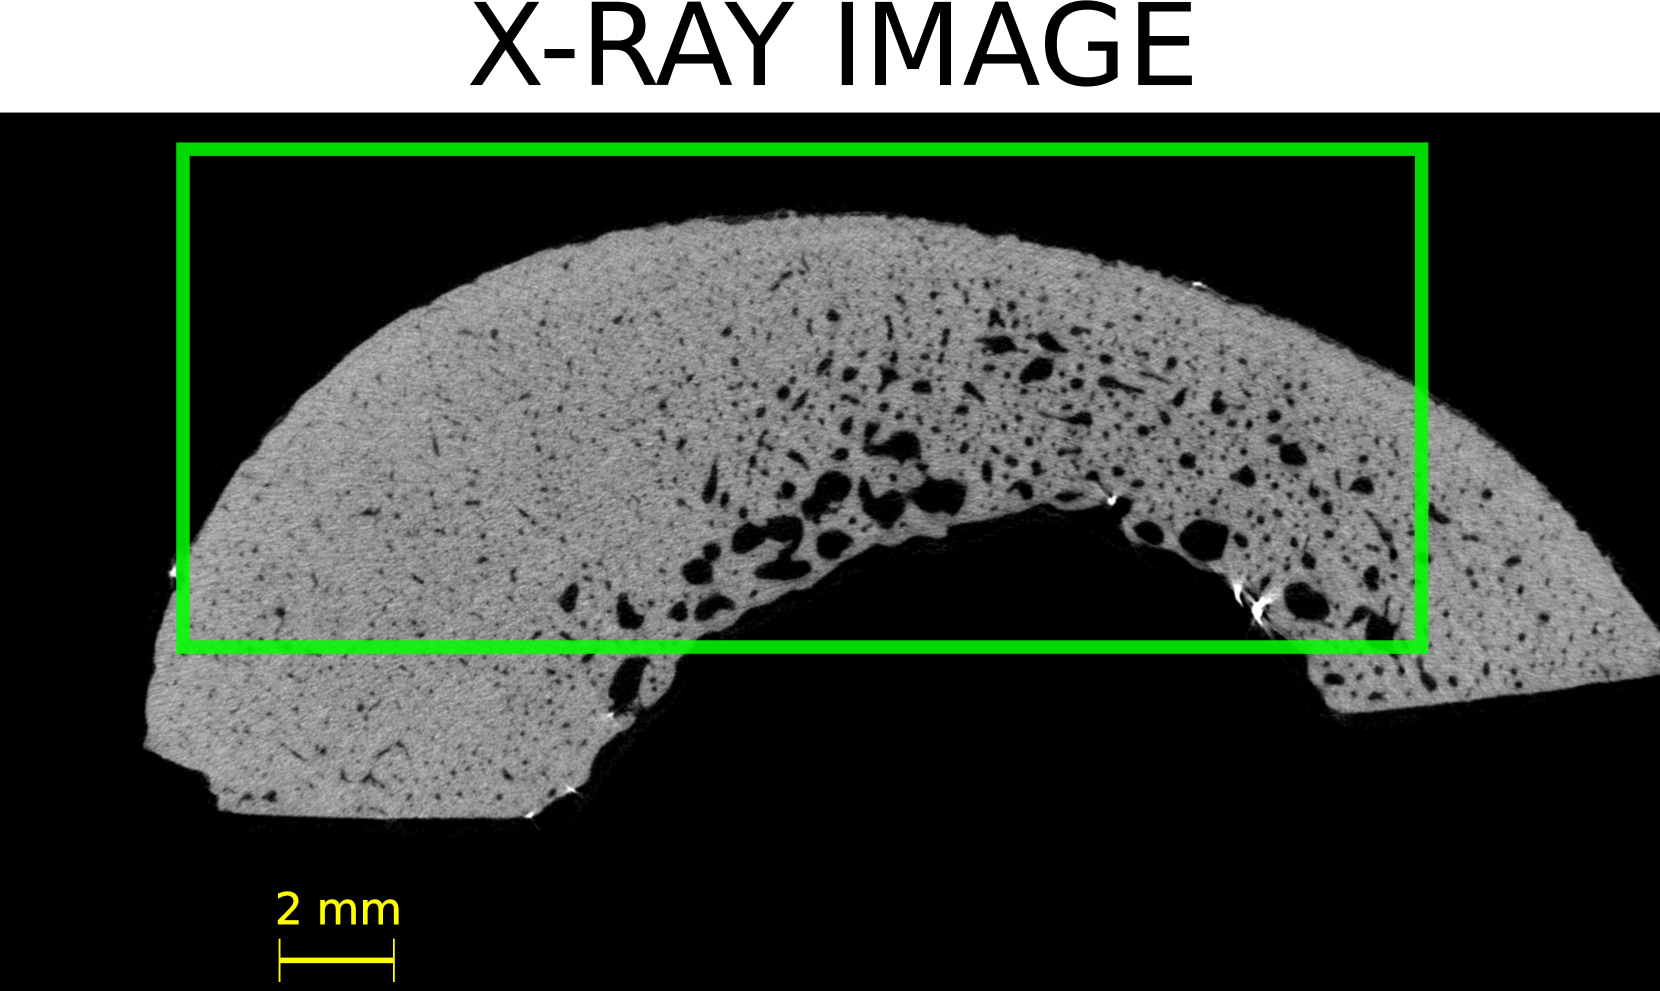

Four volumes of interest (VOI) were defined within the three-dimensional (3D) HR-µCT image of each sample. The thickness (direction of the bone axis) and width of the VOIs were 15 and 20 mm, respectively. The height of the VOIs varied between 8 and 10 mm, depending on the cortical thickness and diameter of each sample. Figure LABEL:method:example_xray_slice shows a two-dimensional (2D) slice in the transverse plane extracted from each VOI for all the samples. The VOI’s dimensions approximately correspond to the thickness (probe elevation direction), lateral dimension (probe aperture) and depth of the US image.

The initial step was to apply a Gaussian filter (round kernel of radius 2 or 3, depending on the sample) to remove acquisition noise. Then, the VOI were binarized using 3D Otsu method [31]. Given that this study focuses on the cortical bone tissue, we removed, in the endosteal region, the bone remnants resulting from a trabecularization [5] of the cortex (samples 4 and 5, see Figure LABEL:method:example_xray_slice and Figure S1 in supplementary materials). To do this, we used kernel filtering (either Kuwahara or Uniform kernels with a radius of 2) and morphological operations to close all pores below a specific threshold diameters, thereby generating a mask that excluded trabecular regions. The specific choice of kernel and parameters varied across samples to accommodate the high morphological variability among the samples (Figure LABEL:method:example_xray_slice).

The 20 VOIs (4 VOIs in each of the 5 samples) showed a great diversity in terms of cortical thickness, porosity, and distribution of pores (Figure LABEL:method:example_xray_slice). Cortical thickness estimated from micro-CT images ranged from 2.5 to 6.3 mm (Table LABEL:table_chap_4:pore_stat_samples_combined). The microstructure parameters are summarized in Table LABEL:table_chap_4:pore_stat_samples_combined. Samples 1 and 2 had the lowest porosity (5–6.4 % and 5.3–6.7 %, respectively) and no large pores (Lg.Po.Dm 175 m). Sample 3 showed moderate porosity (7–12.3 %) with moderately large pores (Lg.Po.Dm in the range 224–228 m). Samples 4 and 5 presented the highest porosity (12.2–16 % and 16.4–16.6 %, respectively) with 10% of the pores with diameter above 300 m. Sample 4 displayed the largest pores (Lg.Po.Dm in the ranged 334–423 m), which can be clearly seen in Figure LABEL:method:example_xray_slice. Porosity values and the porosity gradient from the periosteal to the endosteal surface seen in some samples are consistent with the literature data for elderly donors [27].